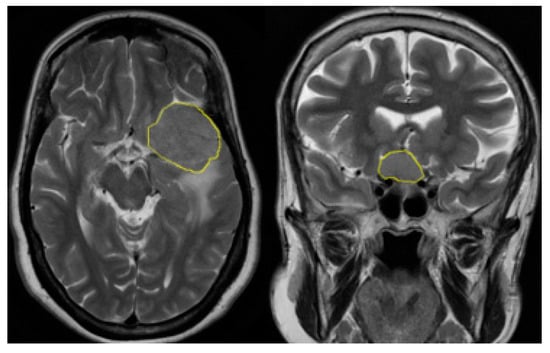

Current medical imaging techniques, notably magnetic resonance imaging (MRI), play a pivotal role in identifying brain tumors [3]. However, challenges persist in precise and swift classification. The proposed YOLO-based approach aims to overcome these challenges by offering a real-time object detection system with the potential for enhanced sensitivity and accuracy. Magnetic resonance imaging (MRI) is an advanced medical scan that utilizes radio waves and powerful magnetic fields to create detailed images of the body’s organs and tissues. Its versatility allows examination of various body parts, including the brain, bones, and heart, making it effective for detecting diverse diseases. MRI plays a crucial role in identifying areas of injury, particularly by visualizing water, a key component of the human body. A water molecule is made up of two hydrogen atoms and one oxygen atom (denoted as H2O). This method relies on the alignment and manipulation of hydrogen nuclei (protons) through powerful magnets and radio frequency, ultimately producing images based on the protons’ behavior in a magnetic field. The resulting signals, generated during a process called precession, are measured and translated into meaningful images [3]. Figure 1 shows a real meningioma classification process with clear labels from the KKUH dataset.

Figure 1.

Two sample MRI images from the KKUH dataset, where the yellow part in the image is the tumor location and the left image exhibits a firm brain tumor and the one on the right discloses a soft brain tumor. The two brain tumors are of type meningioma.